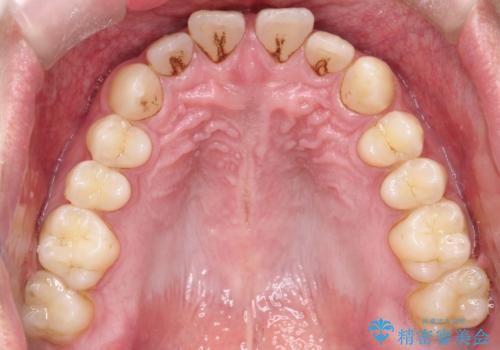

【インビザライン】前歯の隙間を治したい。

- 前歯の隙間を主訴に来院されました。

インビザラインにて治療しました。

ディープバイトも改善でき患者さんも満足されていました。

前歯の隙間だけを閉じる治療を行うだけでは、噛み合わせが悪くなるためディープバイトも改善が必要です。